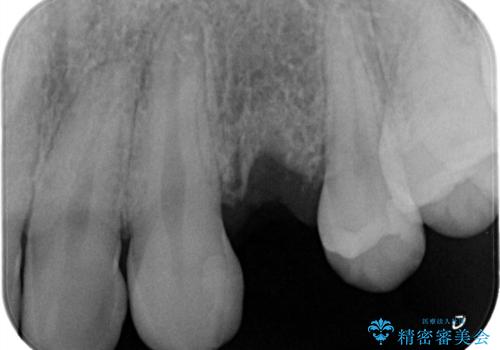

虫歯がかなり進行していて根っこしか残っていない状態でした。日々の歯ブラシが上手く出来ていなくプラーク(細菌の塊)も溜まっている状態でした。

歯を保存するのは出来ないと診断し抜歯した後にインプラントで治療を行いました。